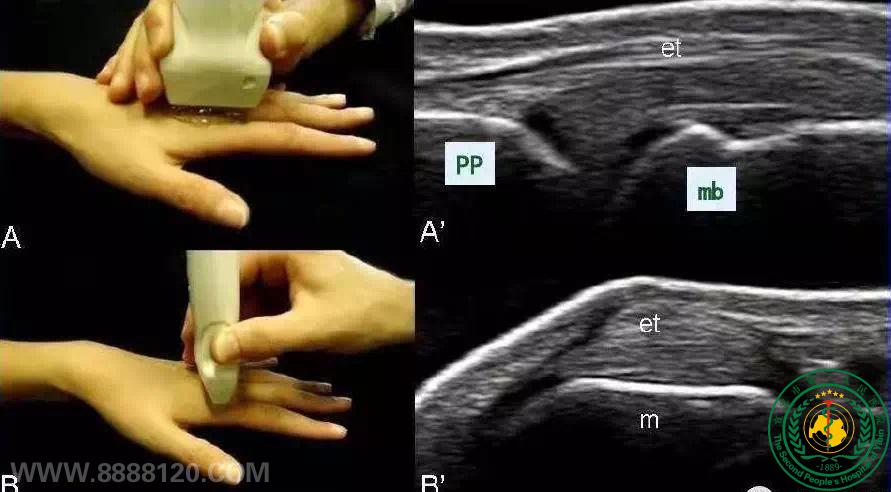

风湿免疫科——肌肉骨骼超声、风湿免疫利器

宜宾市第二人民医院 图文